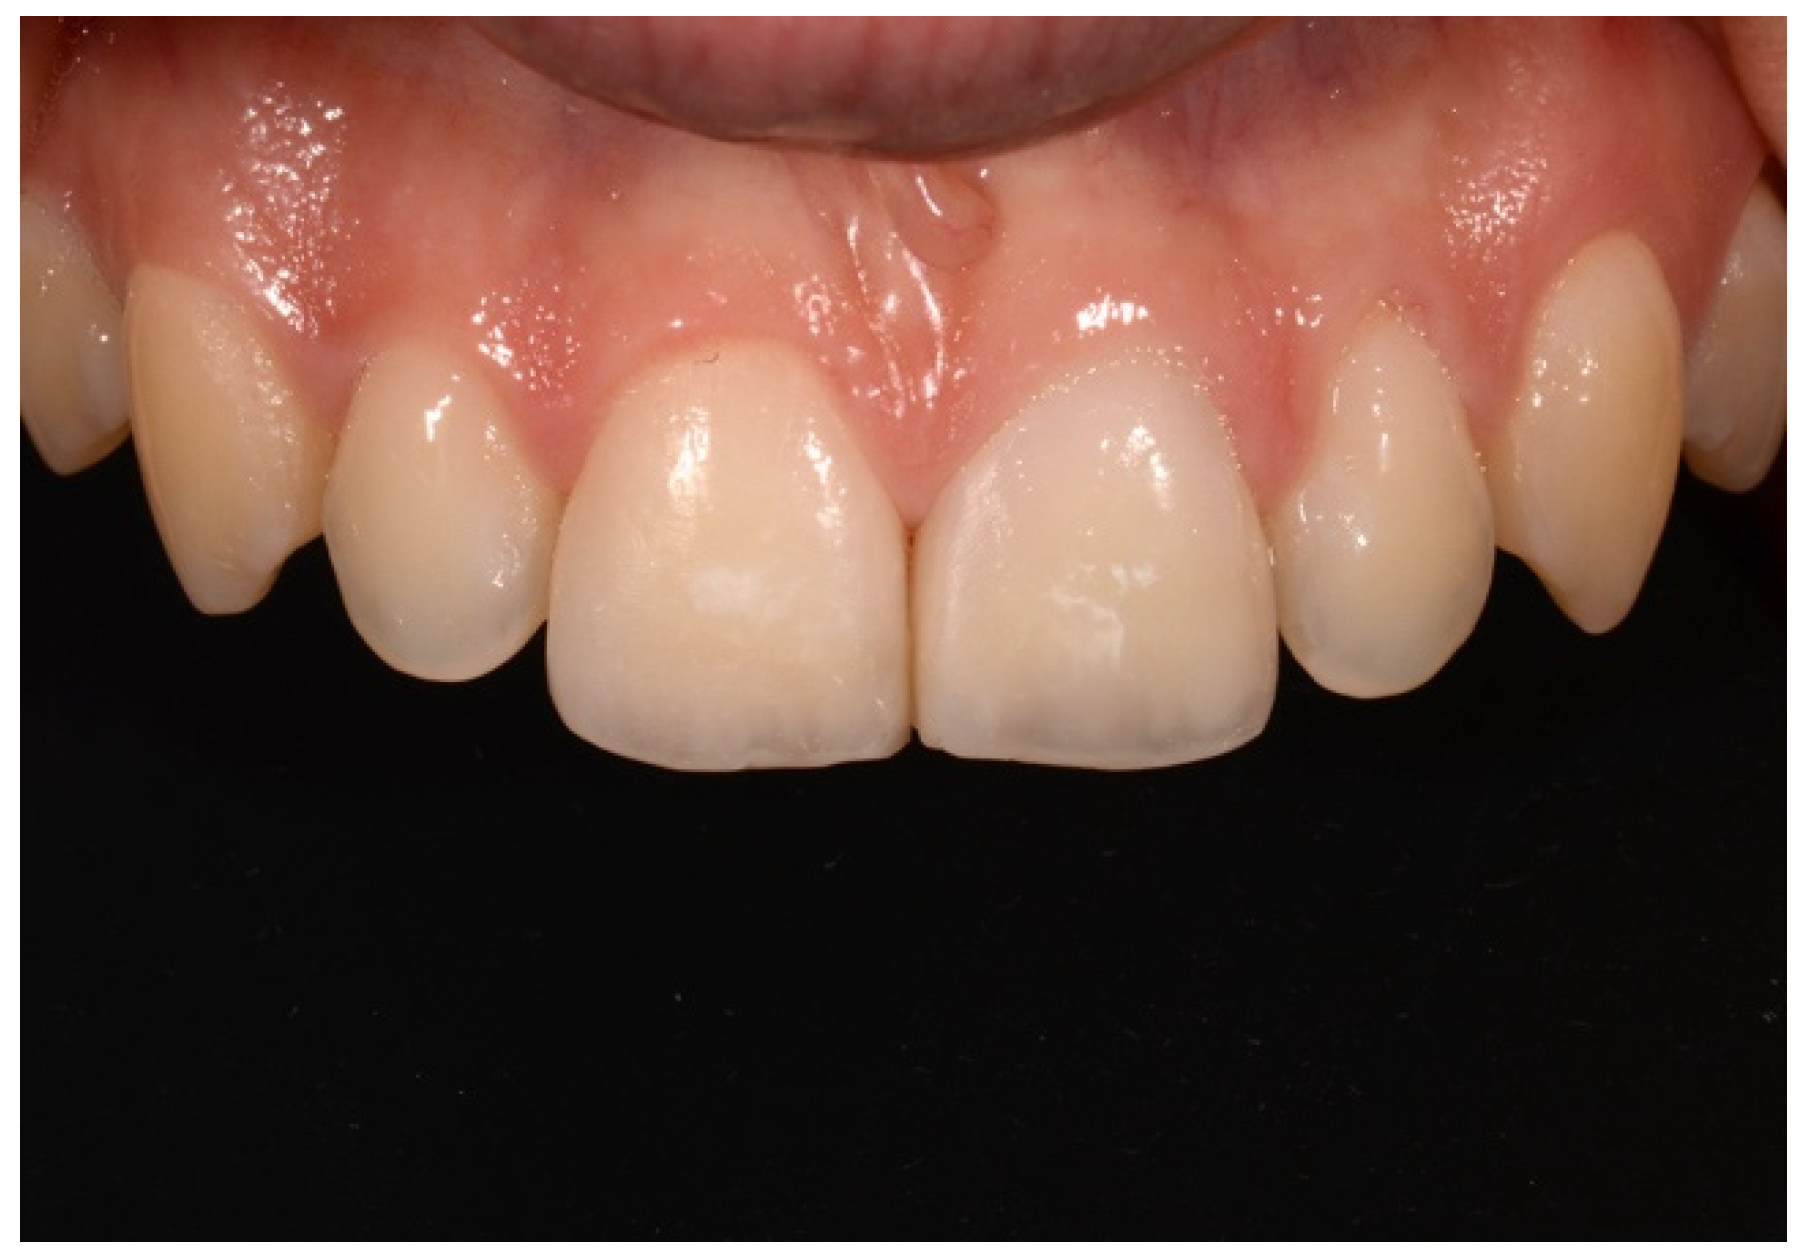

2. Case Presentation